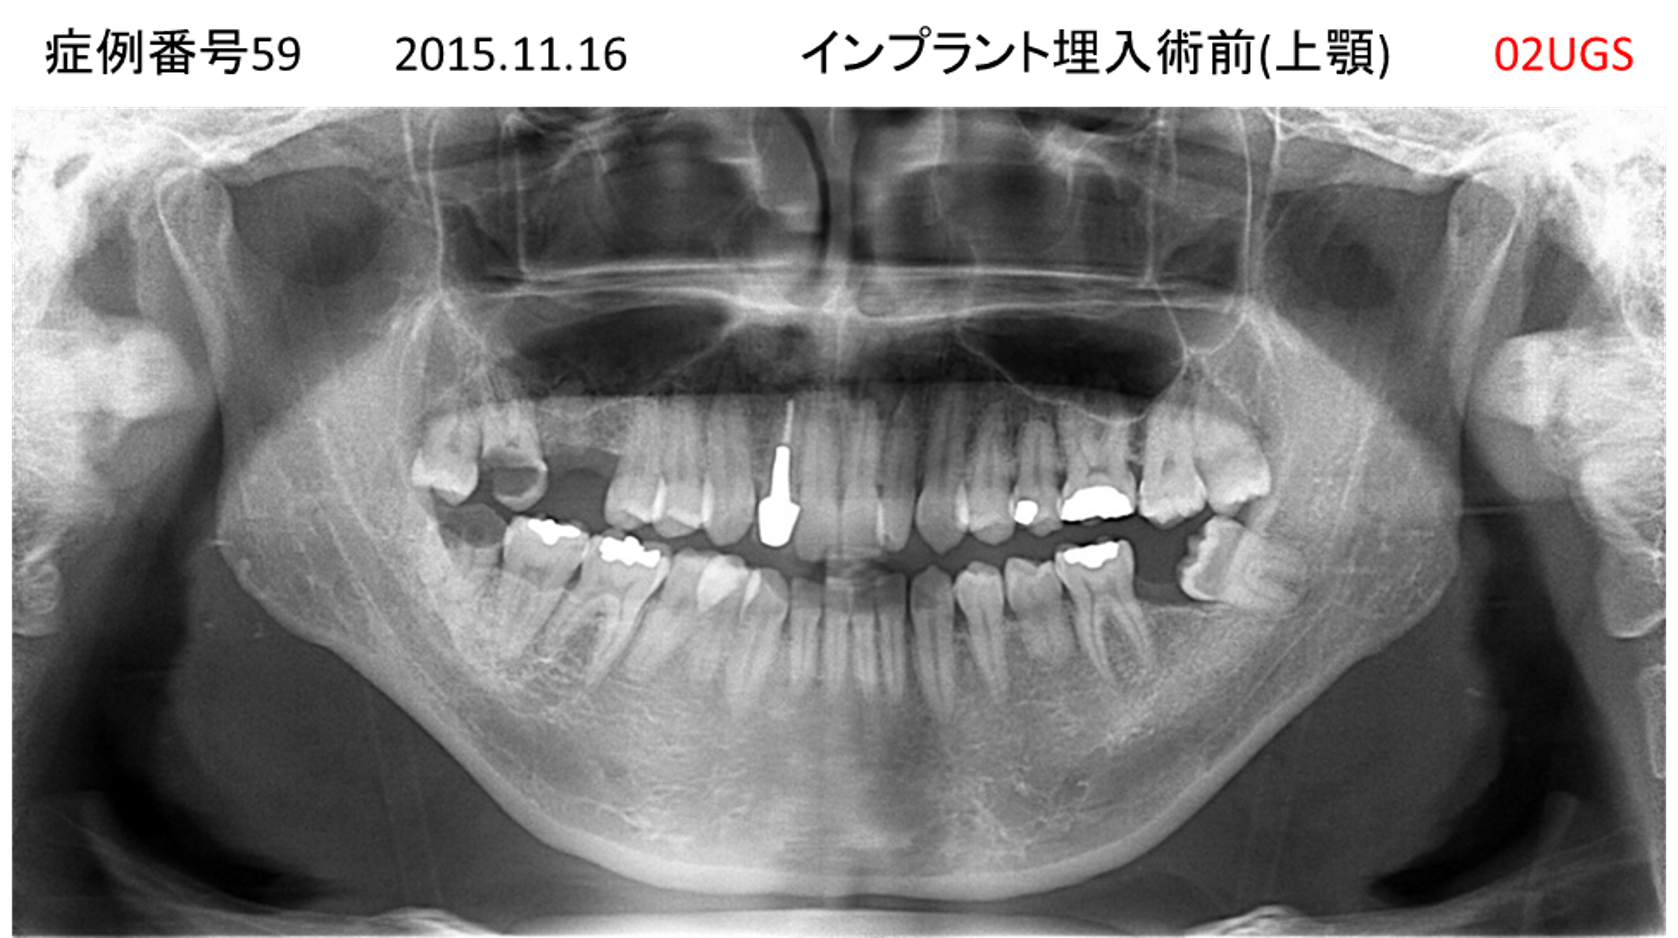

上の前歯がおかしな方向になった患者様のインプラント症例

| 治療名称 |

インプラント |

| 治療費用 |

235万円+税 |

| 治療期間 |

5か月 |

| 患者さんの症状(主訴) |

上の前歯がおかしな方向になった。全く噛めず、最近は食事もまるのみ状態。 |

| 治療内容 |

サイナスリフト インプラント |

| 治療結果 |

見た目がとても良くなった。ご飯が何でも食べることがうれしい。 |

| 治療の注意点(リスク/副作用) |

インプラントが壊れたら再治療が必要 |